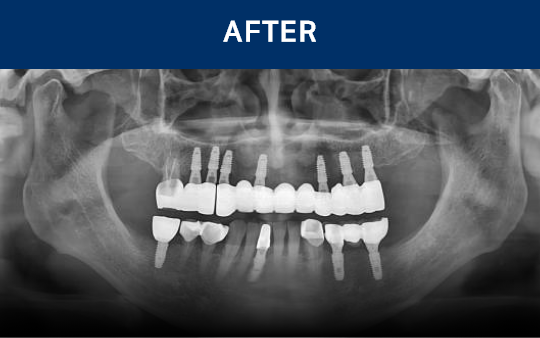

清晰可见的成果,

就是新吉种植牙

科值得信赖的证明.

通过种植牙, 让您无忧进食, 自在微笑, 重拾生活的舒适感

种植牙是在精准诊断与治疗计划的基础上,

通过多个步骤进行的治疗方式

会根据患者的口腔状况, 分阶段安全推进